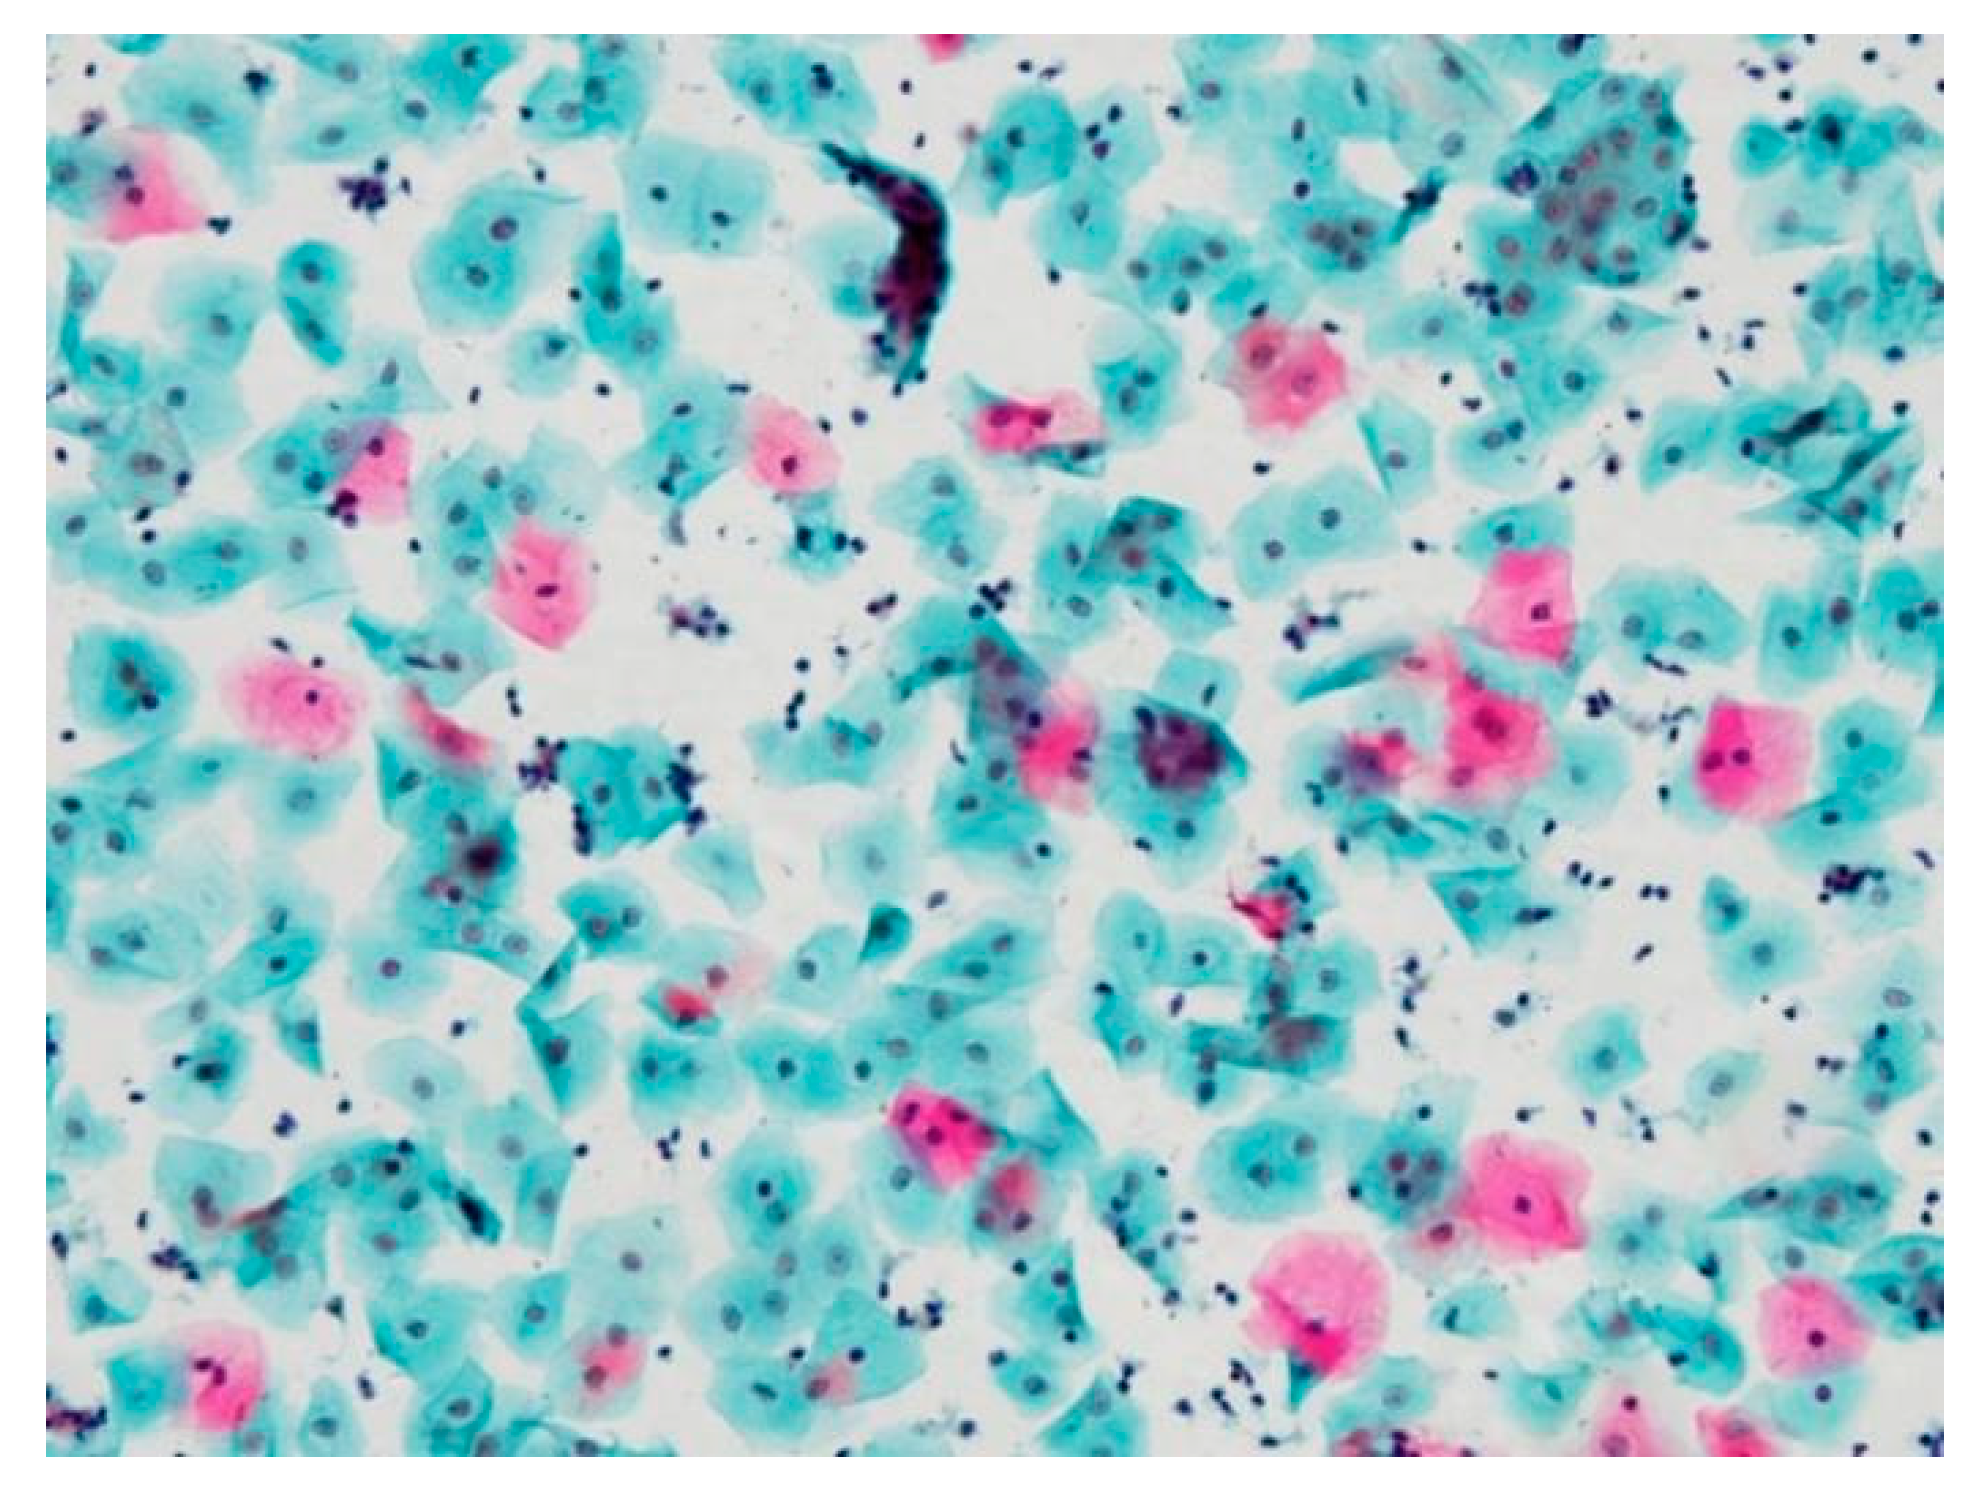

3.1. Pseudo-Color Image Synthesizing and Absorbance Unmixing